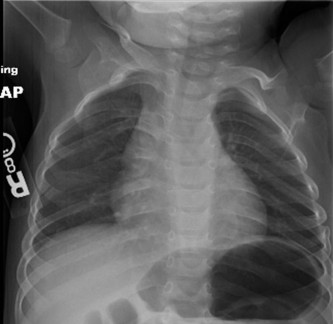

CASE 23 A 2-week-old girl, born to a G1P1 mother, is brought to you for evaluat…